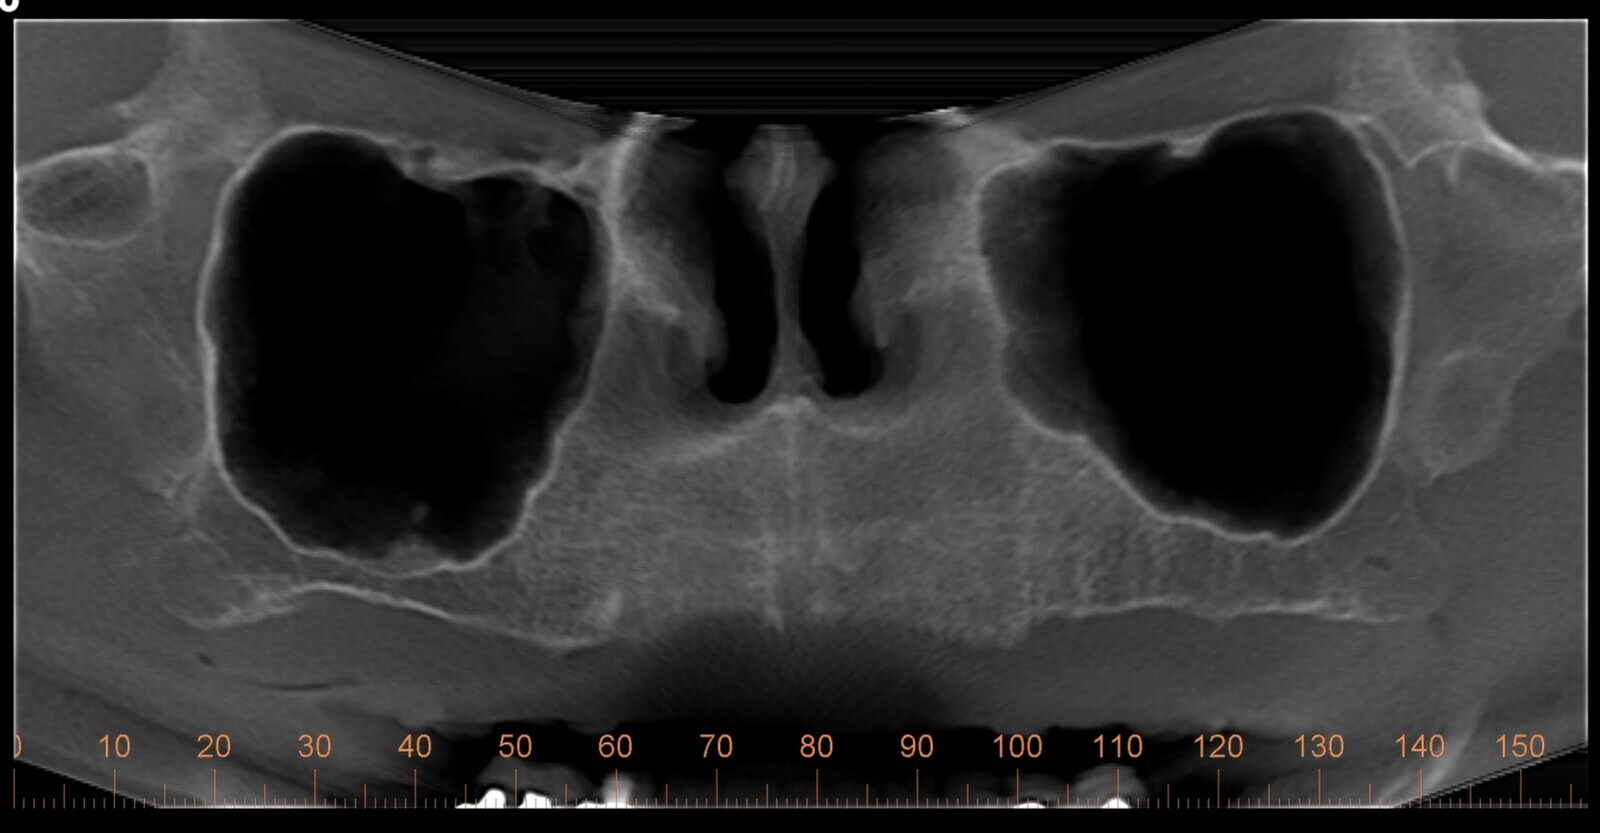

Se realizó un modelo de cera maxilar de acuerdo a los requisitos estéticos y funcionales de la paciente, con el propósito de utilizar su prótesis maxilar como guía radiográfica a través de una tomografía computarizada de haz cónico (CBCT), complementada con la adquisición de objetivos faciales y el STL de la prótesis.

La integración de las imágenes se realizó en el programa de planificación y las relaciones maxilo-mandibulares y quirúrgico-protésicas se evaluaron para determinar las opciones quirúrgicas disponibles para la paciente.

Se observó la permanencia del hueso alveolar con respecto a la pared anterior del seno maxilar y la buena correlación sagital entre los dientes anteriores y la posición de la cresta alveolar, que, aunque era delgada, se encontraba en una relación inmediata, no para sostener implantes convencionales, sino para ser atravesada por un implante cigomático en la posición de los caninos, y la presencia de hueso residual relacionado con la premáxima alrededor del conducto nasopalatino, área esencial para posicionar un implante convencional.

Figura 2. Modelo de planificación quirúrgica.